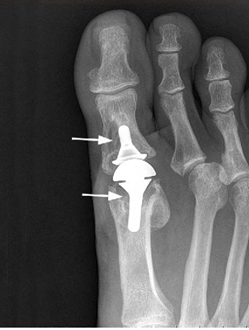

Arthroplasty for Hallux Rigidus

During arthroplasty, the joint surfaces are removed, and an artificial joint is implanted.